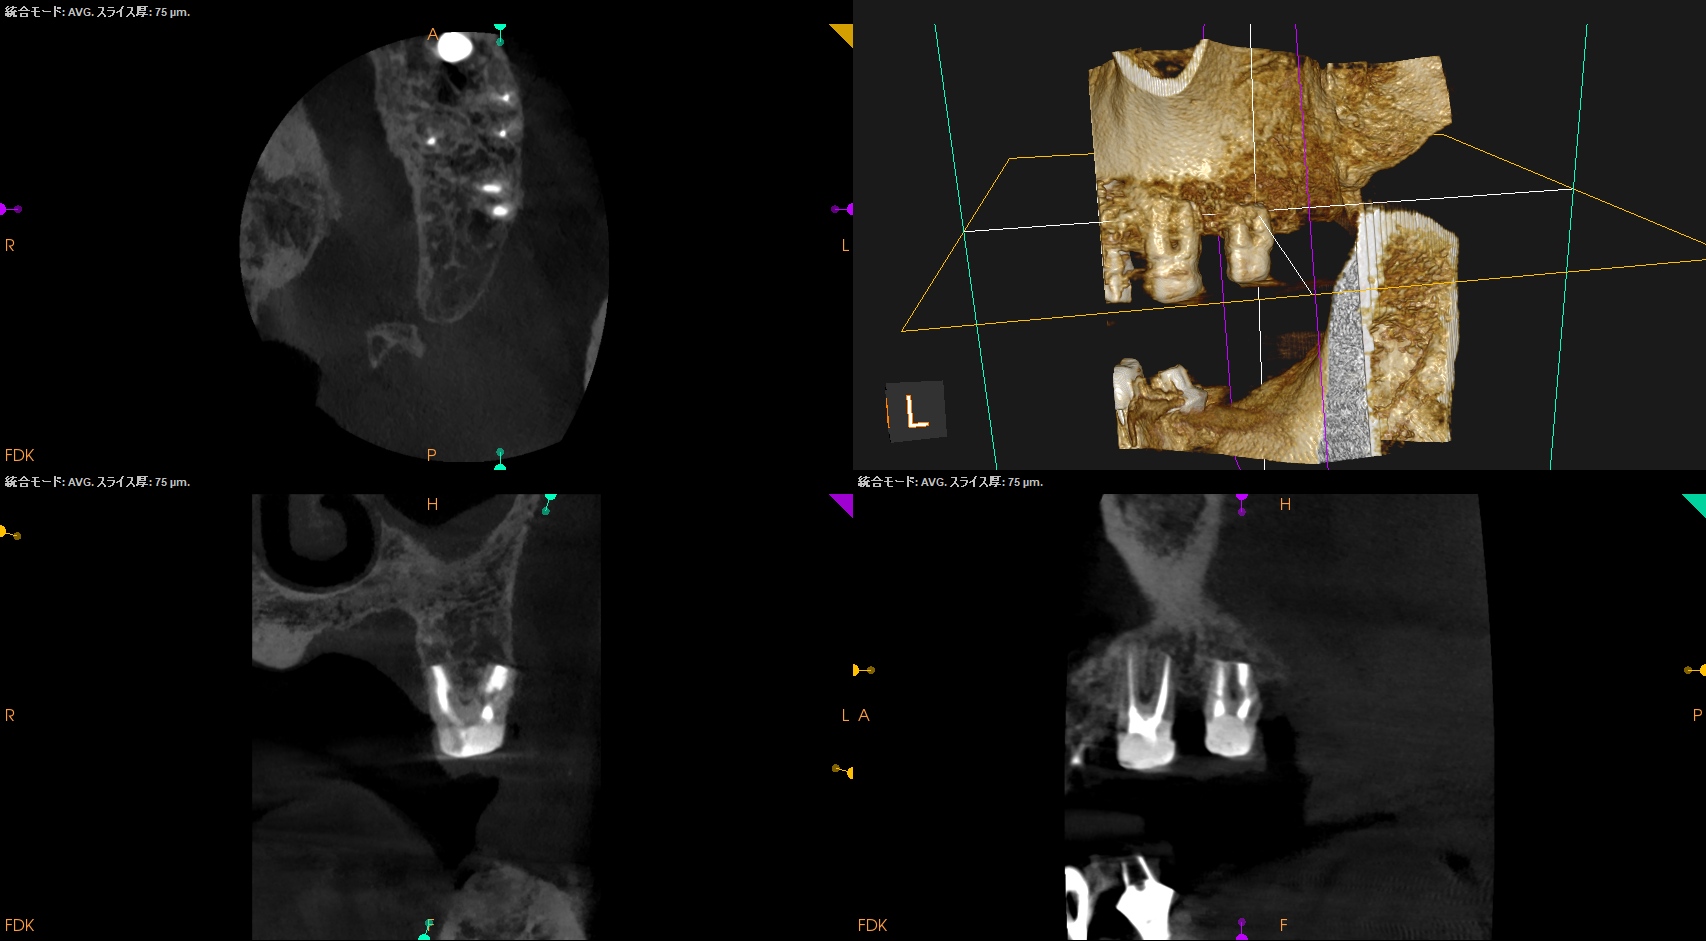

#15 Intentional Replantation 6M recall(2025.10.8)

術直後と比較した。

歯槽骨がだいぶ回復している。